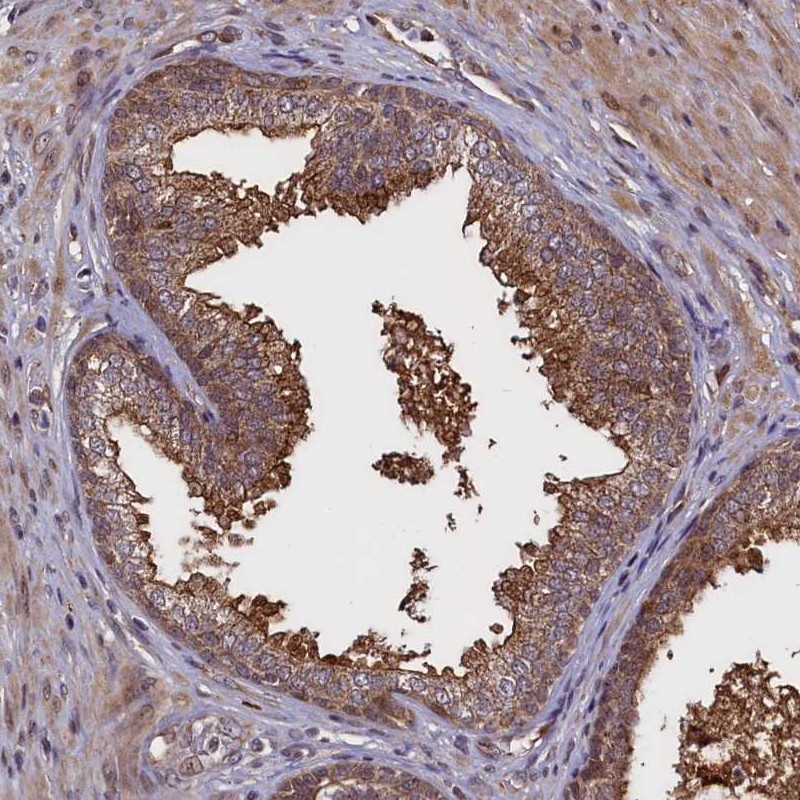

Immunohistochemical staining of human prostate shows moderate cytoplasmic positivity in glandular cells.